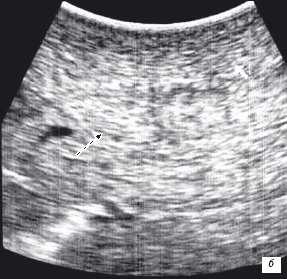

Клинический пример N2. Пациентка Р. находилась на лечении в ГУРОНЦ РАМН. При прохождении обследования был установлен диагноз рак толстой кишки. По данным ультразвуковой компьютерной томографии на фоне выраженной диффузной неоднородности паренхимы печени очаговые образования не определялись. При проведении ангиографии и компьютерной томографии так же убедительных данных за наличие метастазов в печень получено не было. При интраоперационном ультразвуковом исследовании были выявлены два очага, характерными особенностями которых являлись малые размеры (0,2 - 0,4 см), а так же нечеткость контуров и изоэхогенность структуры (рис. 1 а,б).

Рис. 1. Метастатические очаги (стрелки) в печени при интраоперационной ультразвуковой томографии.